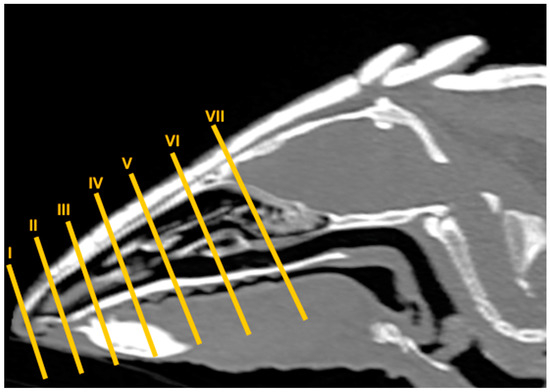

2.2. CT Technique

3.2. Computed Tomography (CT)